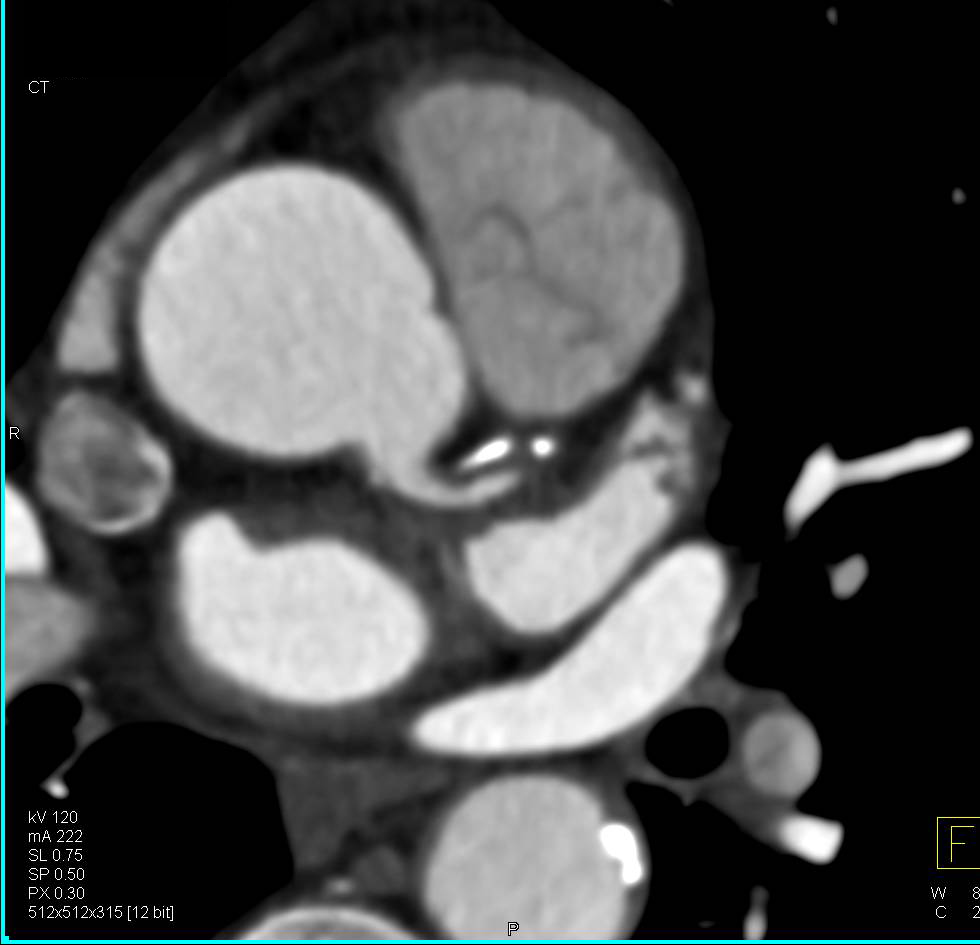

Aortic Stenosis with AV Calcification